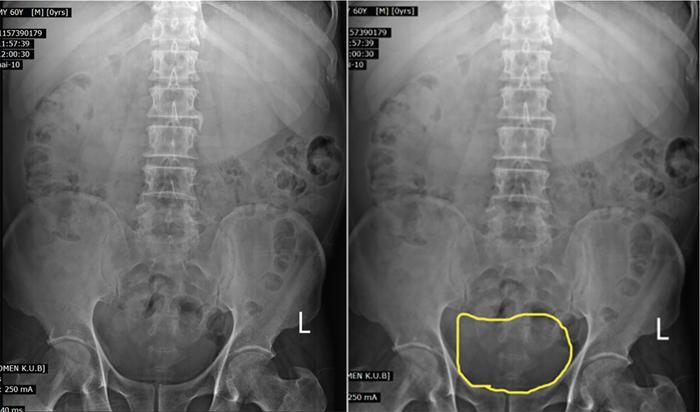

Ovarian cyst in plain radiograph is noted on one side of the pelvis. Areas of calcification can be demonstrated.

Plain radiograph (Fig. 11.4.1.1) shows a midline opacity arising from the pelvis extending above the pubic symphysis which gets relieved on catherization.